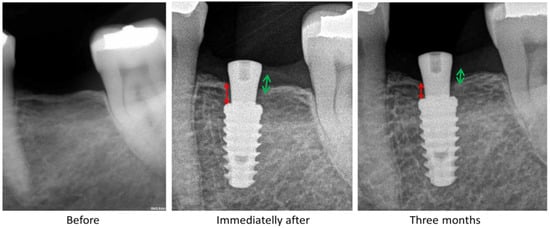

The comparative data measured between mesial and distal marginal bone loss with the observed variables. Overall mean of mesial and distal MBL were 1.11 ± 1.16 mm and 1.11 ± 1.15 mm, respectively, resulted in non-statistically significant differences (p > 0.05). The comparison of the bone loss between the patient’s sex showed non-statistically significant differences (p > 0.05), where the woman patient’s show an MBL mean value of 1.1 ± 1.25 mm and the man patient´s 1.0 ± 0.93 mm. The images of the Figure 6 show a sequence of measurements of the MBL.

Figure 6.

Radiograph sequence used to evaluate and measure the bone level. The measurements were performed from the implant platform to the crestal bone (red arrows = m-MBL and green arrows = d-MBL).